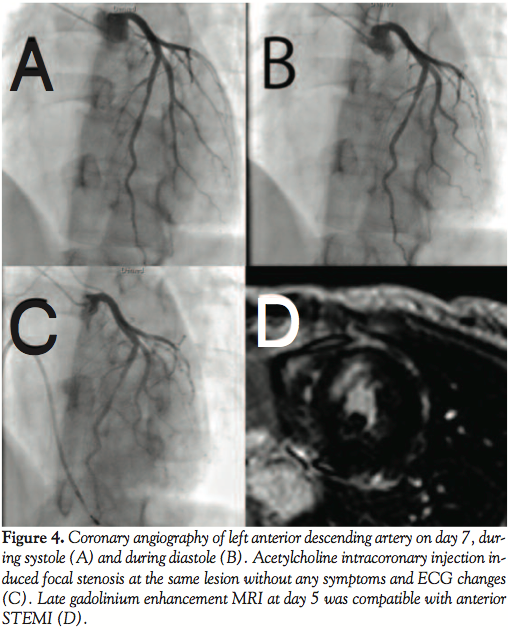

and performed emergent coronary angiography (CAG). CAG showed normal right coronary artery, left circumflex artery, and myocardial bridge at the mid-portion of the left anterior descending artery (Figures 2A and 2B). We had to confirm that the etiology of left ventricular wall motion abnormalities was not due to plaque rupture, but due to myocardial bridging, in order to decide further management. We applied OCT to render a decision. OCT showed smooth internal coronary artery wall at the bridge

ventricular fibrillation caused by ST-elevation myocardial infarction (STEMI) due to myocardial bridging and focal spasm, with no clinically significant stenosis in the bridge lesion. We prescribed 200 mg Ca-antagonist, diltiazem, twice a day and 15 mg nicorandil 3 times a day. Clinical course, serial ECG findings, and late gadolinium enhancement MRI at day 5 were compatible with anterior STEMI (Figure 4D). Laboratory data were as follows: cardiac troponin T was 1.6 ng/mL on admission, and the peak serum creatine kinase level and creatine kinase MB isoenzyme were 421 IU/L and 47 IU/L, respectively, 10 H after symptom onset. Repeated coronary angiography at day 7 showed dilatation of the bridge (Figure 4A and 4B). Acetylcholine intracoronary injection induced focal stenosis at the same lesion without any symptoms and ECG changes (Figure 4C). We judged that no clinical ischemia could be induced with the medications. On day 8, the patient was discharged and remains well after 2 years.